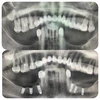

الدكتورة سيفيم شاكيليطاش طبيبة أسنان

مجالات التخصص

طب الأسنان